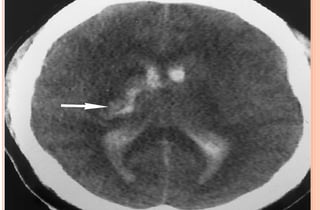

PHOTOS OF CT EVALUATION OF

PREGNANT WOMAN WITH TRAUMA– CT

SCANS DONE AS A PART OF INVESTIGATIONS

DONE IN EMERGENCY --- MATERNAL HEAD

AND ABDOMEN AS PER NEED OF INDIVIDUAL

CASE ---WITHOUT FEAR OF X RAYS

EXPOSURE TO FETUS IN UTERO

PHOTOS OF CTEVALUATION OF PREGNANT WOMAN WITH TRAUMA– CT SCANS DONE AS A PART OF INVESTIGATIONS DONE IN EMERGENCY --- MATERNAL HEAD AND ABDOMEN AS PER NEED OF INDIVIDUAL CASE ---WITHOUT FEAR OF X RAYS EXPOSURE TO FETUS IN UTERO